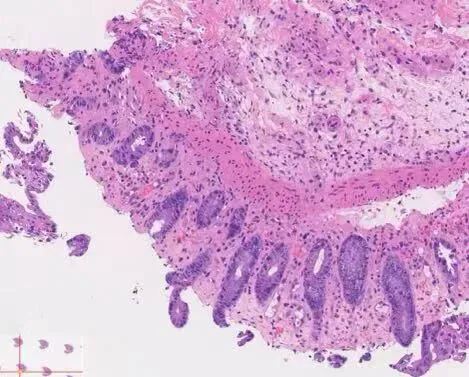

图1:缺血性肠炎:黏膜表层损伤(糜烂),隐窝黏液丢失,隐窝萎缩

组织学形态

表层黏膜:显著损伤、脱落

隐窝:黏液减少、杯状细胞减少,“萎缩”的微小隐窝,残余腺体排列更紧密

固有层:玻璃样变(透明变),正常疏松结缔组织被致密嗜酸性基质替代,可见浆细胞、淋巴细胞、嗜酸性粒细胞浸润,伴固有层崩解